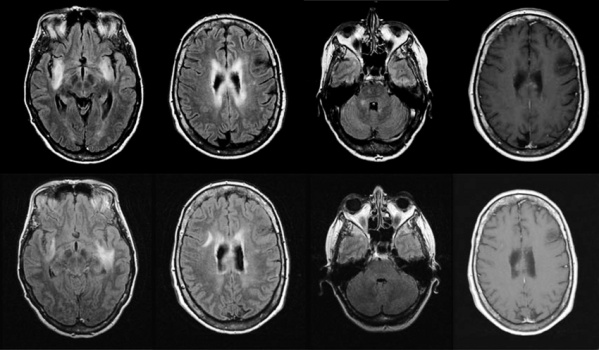

Esta patología neurológica óptica, cuyo diagnóstico es más frecuente en las mujeres de entre 20 y 30 años, es un trastorno del sistema nervioso central que se produce cuando las defensas del organismo se confunden y atacan estructuras propias, impactando principalmente en los nervios del ojo (neuritis óptica) y la médula espinal (mielitis).

“El organismo reconoce algo propio como si fuese extraño y se genera una respuesta inflamatoria (conocida como recaída o brote) contra esa estructura. Si no se controla al sistema inmune, este proceso tiene altas probabilidades de repetirse”, aseguró el doctor Juan Ignacio Rojas, coordinador de la Unidad de Esclerosis Múltiple y enfermedades desmielinizantes del CEMIC (MN 115.414).

Según el experto, entre los síntomas de esta enfermedad se pueden enumerar: fatiga, dolor, debilidad muscular, imposibilidad para caminar y ceguera. “Se trata de una afección caracterizada por las recaídas o brotes, que pueden generar un daño irreversible y discapacidad. Las recaídas pueden generar daño neurológico irreversible y acumulativo, provocando una limitación en las capacidades de la persona”, resaltaron.

“Las inflamaciones o recaídas pueden ser muy severas, con poca recuperación en algunos pacientes, por eso se la considera una enfermedad que puede ser, en algunas situaciones, muy incapacitante llevando a algunas personas afectadas a necesitar una asistencia para deambular al poco tiempo de haber comenzado con la patología”, resaltó Rojas.

Aunque se desconoce la causa de la enfermedad, los investigadores lograron determinar que la respuesta autoinmune contra los nervios ópticos y contra la médula espinal es propiciada por una proteína llamada interleuquina 6 (1L-6). Tal fue su hallazgo que, en la actualidad, ésta ya es considerada como uno de los factores desencadenantes de la neuromielitis óptica.